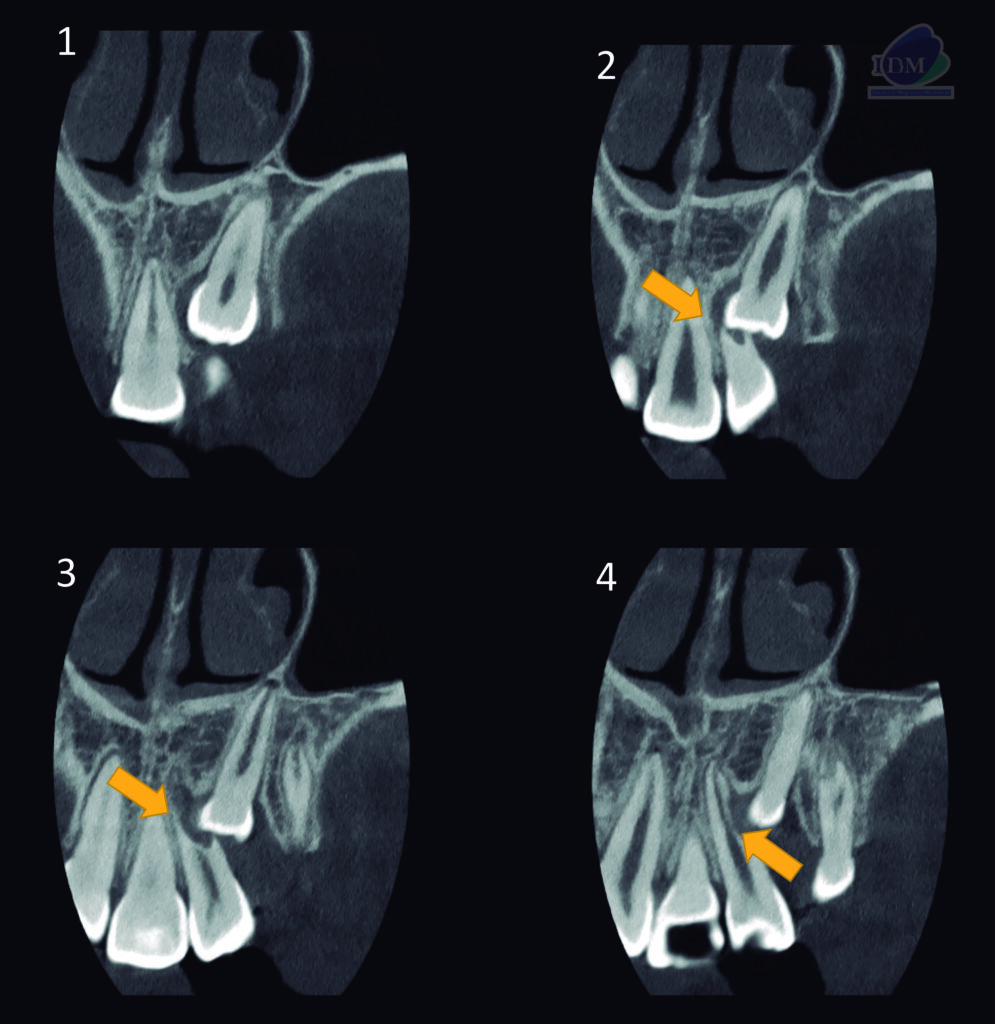

A la evaluación de la tomografía computarizada de campo reducido se observa la porción coronaria de la pieza 23 orientada hacia vestibular y ocasionando el desplazamiento palatino de la pieza 22 así como la reabsorción radicular externa vestibulodistal del tercio medio que también compromete conducto pulpar. Finalmente se observa el tercio apical de la pieza 23 en formación y en contacto con el piso de fosa nasal y seno maxilar.

CORTES TANGENCIALES

CORTES TRANSAXIALES